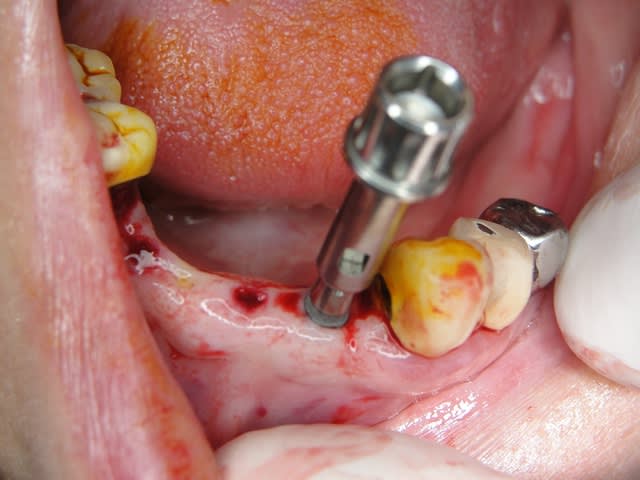

Implantation immédiate 26.Technique simplifiée

Exp dans ce cas 4,5/10mm en 36 dans un site d'extraction récent placé en 12mm soit deux millimètres plus profondément j'ai scellé un prep cap angulé 5 degrés niveau 1/0 dont la limite s'arrête à la rainure de la tête carrée, pour 37 3,5/10mm placé en 10mm j'ai utilisé un prep cap 2/2mm. On prend vite l'habitude moi j'utilise que 2 modèles en zircone et 3 en titane..